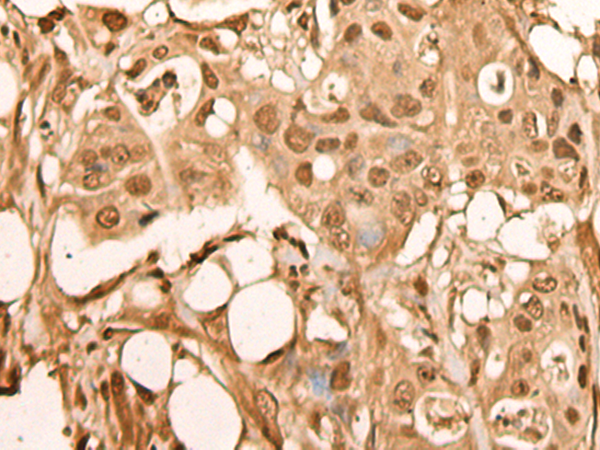

IHC (Immunohiostchemistry)

(The image on the left is immunohistochemistry of paraffin-embedded Human colorectal cancer tissue using 46356(BRF2 Antibody) at dilution 1/40, on the right is treated with fusion protein. (Original magnification: x200))